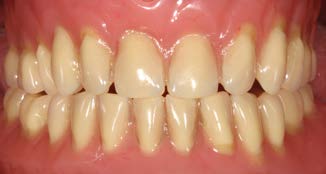

Nghiên cứu cũng ghi nhận sự thay đổi rõ rệt ở bệnh nhân nữ muốn điều trị Implant vùng hàm dưới nhưng gặp hạn chế vì tiêu xương dọc quá lớn và hàm giả lỏng lẻo.

3.2. Lên kế hoạch mô phỏng và ứng dụng Implant ngắn 6.5mm BTI